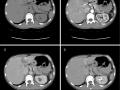

Hemangioma Hepático Típico

Fev de 2021.

11.695

tomografia computado...